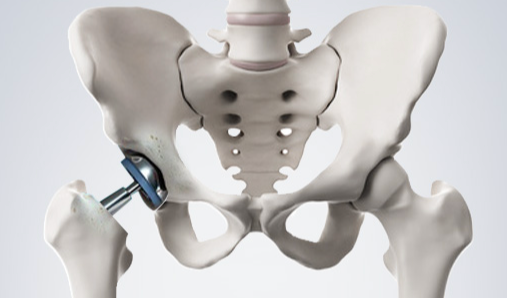

고관절 치환술(Total Hip Arthroplasty)

적응증: 고관절 치환술은 고관절 골관절염, 류마티스 관절염, 무혈성 괴사 또는 고관절 골절이 있는 개인에게 일반적으로 수행됩니다.

절차: 고관절 치환술 중 손상된 고관절의 볼-소켓 구성 요소를 인공 부품으로 교체합니다. 이 절차는 다양한 수술적 접근법을 사용하여 수행될 수 있습니다.

혜택: 고관절 치환술은 통증을 완화하고 고관절 기능을 회복하며 환자가 독립성과 이동성을 회복할 수 있도록 해줍니다.